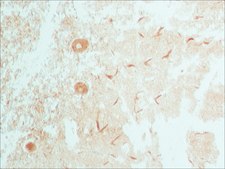

immunohistochemistry (formalin-fixed, paraffin-embedded sections): 1:50-1:100 using biotin/ExtrAvidin®-peroxidase staining of heat-retrieved sections of human cerebellum, immunoprecipitation (IP): 2-4 μL using rat NRK and mouse 3T3 cell lysates

Rabbit Anti-ATG3 (C-terminal) antibody recognizes human, rat, and mouse Atg3 by immunoprecipitation (approx. 36kDa) and immunohistochemistry. Detection of the Atg3 staining by immunohistochemistry is specifically inhibited with the immunizing peptide.